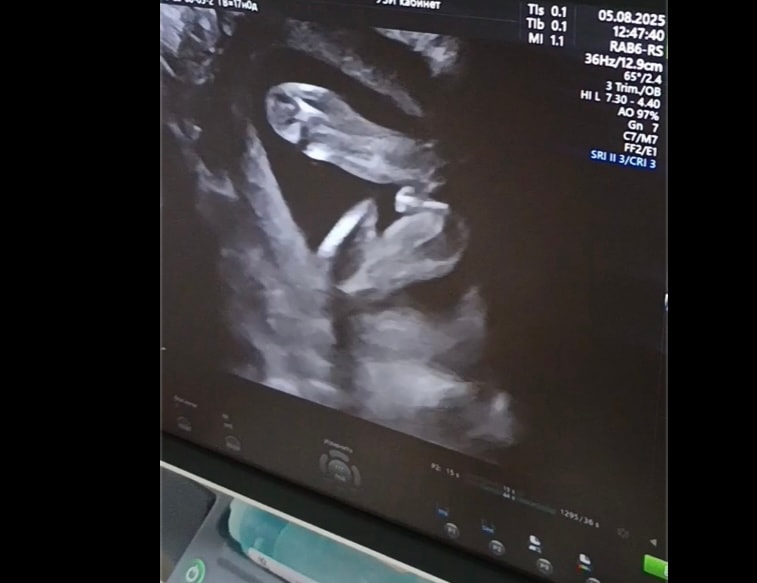

Изображение Изображение

Василиса , я вижу мошонку. Мои девочки выглядели по-другому на УЗИ. Там было чёткое кофейное зёрнышко. По центру была темная полосочка, а не светлая